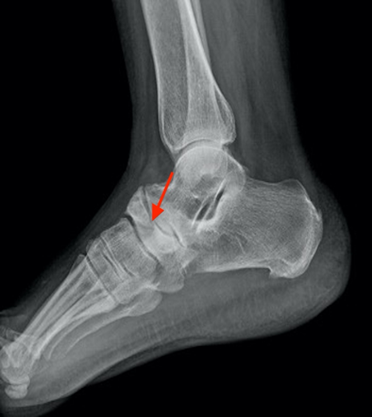

- midfoot: when the

navicular bone’s lateral half falls down, it becomes sclerotic and takes the

aspect of a comma or hourglass (figure 2).

This along with the aforementioned medial subluxation of the talus head,

creates a talo-navicular articulation.

Figure 2. Lateral radiograph of the forefoot revealing a

sclerosis and densification of navicular bone (red arrow).